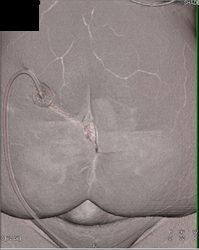

Normal Brachial Artery